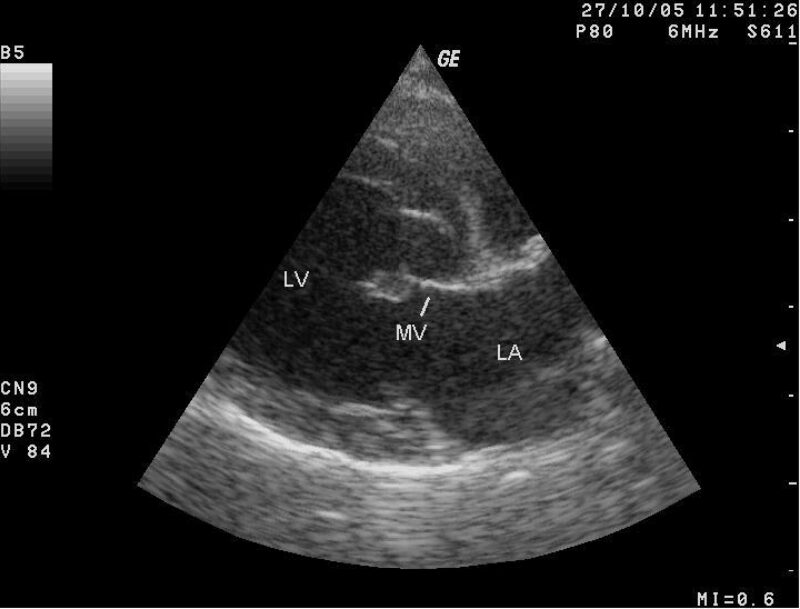

Es gibt viele erworbene, d.h. im Laufe des Lebens entstehende Krankheiten und angeborene Defekte. Die häufigste erworbene Herzerkrankung des Hundes ist die sogenannte „Chronisch degenerative AV-Klappenerkrankung‘‘, häufig auch „Mitralklappenendokardiose" genannt. Diese Erkrankung betrifft vorwiegend kleinere Hunde, wobei manche Rassen, wie beispielsweise der Cavalier King Charles Spaniel, häufiger betroffen sind als andere. Infolge dieser Erkrankung kommt es über verschiedene Mechanismen zur Undichtigkeit einer oder beider Herzklappen, welche die Vorhöfe von den Hauptkammern trennen. Das Blut fließt im Herzen üblicherweise wie in einer Einbahnstraße. Ist dies durch undichte Klappen nicht mehr gewährleistet, fließt bei jedem Herzschlag Blut zurück in die falsche Richtung. Dieses sammelt sich dann zunächst im linken Vorhof und später auch in der linken Kammer, was zur Volumenüberladung des Herzens und letztlich meist zur Auslagerung dieser Flüssigkeit in die Lungen führt. Spätestens dann kommt es zu wahrnehmbaren Symptomen. Die Hunde husten, hecheln vermehrt, sind nicht mehr so leistungsfähig, stellen das fressen ein und werden zunehmend apathischer. Manche Hunde zeigen sogar Ohnmachtsanfälle. Meist fällt jedoch dem aufmerksamen Tierarzt bereits schon früher bei einer Routineuntersuchung ein Herzgeräusch auf.

Es bleibt zu erwähnen, dass Tiere mit Verdacht auf ein Herzproblem spezialisierten Tierärzt:innen vorgestellt und mittels Herzultraschall untersucht werden sollten. Nur so sind eine genaue Diagnose und zielführende Therapie möglich. Wie eingangs erwähnt, ist Herzerkrankung nicht gleich Herzerkrankung.